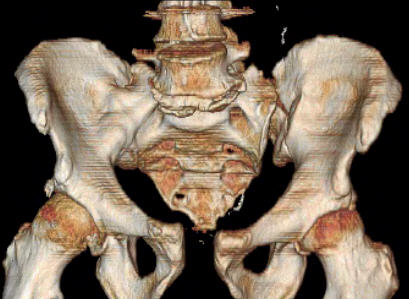

Was hemodynamic unstable at local ER, sent to our Trauma center where circumferential pelvic binder placed and pt. stabilized with fluid, blood, and rewarming. Angiography not performed. An extraperitoneal bladder disruption was found, uro elected to treat non-operatively. Initial xray (not shown) demonstrated 5-7 cm wide at symphysis and SI joint. The first image attached is of CT once binder is in place.

On post trauma day 5 the pt was taken to OR for ORIF of his iliac wing fracture and SI dislocation. The swelling/3rd spacing of fluid in the area of symphysis was profound, but quite acceptable posteriorly.